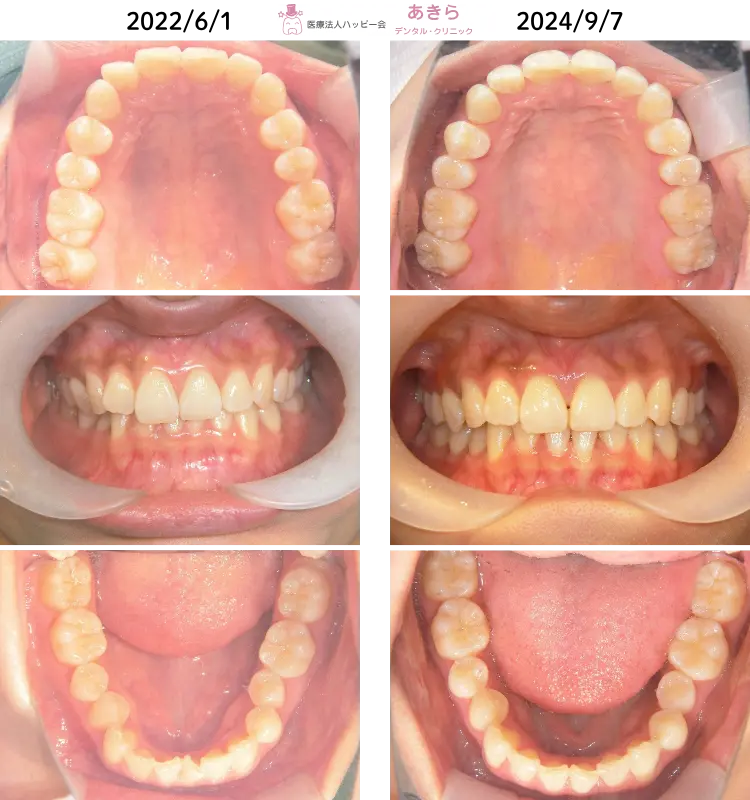

SH療法-症例-No.006-上下前歯部叢生(凸凹)を伴うケース

SH療法の概要 過蓋咬合を伴なう症例 主訴~経過 初診 2022年 6月1日 ⇒ 2024年 10月… -